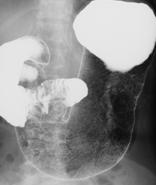

| 食道・胃・腸などの消化管臓器は単純X線撮影では、周りの臓器とのX線の吸収差が小さいため、はっきりした画像を撮影することができません。そこで、X線の吸収が大きなバリウム液等の造影剤と呼ばれる薬剤を入れ、画像の濃淡がはっきり出る状態にして撮影します。また、日本で開発された、バリウム液と空気や発泡剤のガスを利用した、『二重造影法』といわれる検査法は、消化管粘膜の状態を詳細に描出できるので、早期の病変の発見に大きな成果を上げています。 | ![]() |

| 胃の二重造影像 |